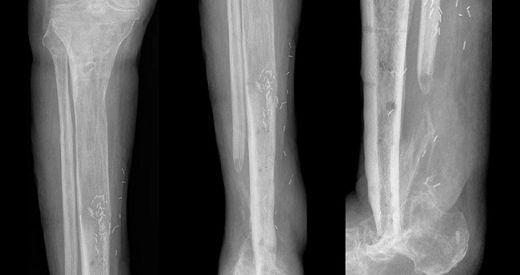

Tanı Yöntemleri Kemik enfeksiyonunun tanısı, klinik değerlendirme ve çeşitli görüntüleme yöntemleriyle konulmaktadır. Tanı yöntemleri arasında: